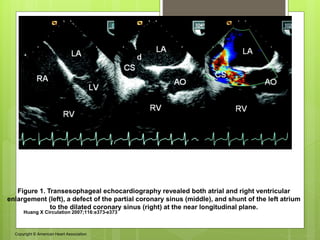

Figure 1. Transesophageal echocardiography revealed both atrial and right ventricular

enlargement (left), a defect of the partial coronary sinus (middle), and shunt of the left atrium

to the dilated coronary sinus (right) at the near longitudinal plane.

Huang X Circulation 2007;116:e373-e373

Copyright © American Heart Association